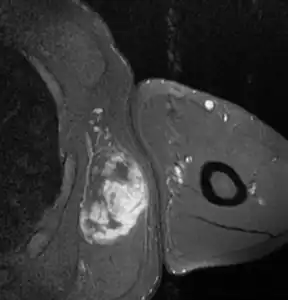

Micrograph of myxoid liposarcoma. H&E stain MRI of myxoid liposarcoma of high grade, in left axillary region of 40 year old man. Horizontal section.

MRI of myxoid liposarcoma of high grade, in left axillary region of 40 year old man. Horizontal section.